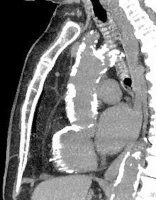

Die koronare Bypassoperation – Indikationen, Risikoabwägung, neue Techniken und Nachsorge // Coronary bypass surgery – Indications, risks, new techniques and postoperative care

Journal für Kardiologie - Austrian Journal of Cardiology 2022; 29 (9-10): 254-256 Volltext (PDF) Summary Abbildungen